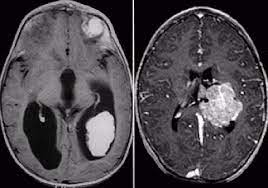

Перед началом лечения обязательно проведение комплексной диагностики, которая позволит не только подтвердить диагноз, но и получить все необходимые сведения о заболевании. В качестве основных методов диагностики используется КТ и МРТ, в том числе с введением контрастных веществ.

Это доброкачественная опухоль, которая чаще всего диагностируется у детей до трех лет. Такое заболевание представляет собой нейроэктодермальную опухоль, располагающуюся внутри желудочков головного мозга и развивающуюся из эпителия сосудистых сплетений желудочков головного мозга. Самое распространенное место локализации – боковые желудочки.

Это достаточно редкое заболевание, на которое приходятся порядка 1% всех случаев опухолей головного мозга у детей. В большинстве случае образование локализуется в боковых желудочках, чуть реже – в четвертом желудочке, и в каждом десятом случае в третьем желудочке. В основном заболевание встречается у детей в возрасте до трех лет. Однако известны случаи его диагностирования у подростков, а также в уже зрелом возрасте.